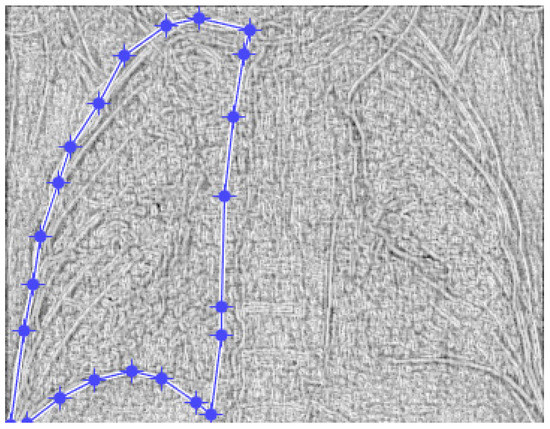

Figure 2 and Figure 3 show the selection of the lung portion of interest for patient MT and the same image in “Invert color” format.

Figure 4 and Figure 5 present the defined masks for the left lung and right lung, framed in blue borders.

Figure 2. The selection of the portion of interest of the lungs of patient MT.

Figure 4. Defining the mask for the left lung of the first patient.

Fractalfract 07 00285 g004

Figure 5. Defining the mask for the right lung of the first patient.

Fractalfract 07 00285 g005